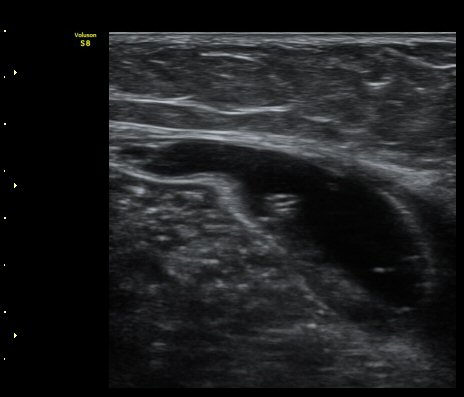

¹«¸ ¾Æ·¡ ÀåµýÁö Á¾´Ü¸é°Ë»ç¿¡¼ ÇÇÇÏ ¿¬ºÎÁ¶Á÷°ú ºñº¹±Ù »çÀÌ¿¡ ¼ö¾×Àú·ù(º£ÀÌÄ¿¾¾ ³¶Á¾ÀÌ ÅÍÁ®¼ Èê·¯³ª¿Â)°¡ °üÂûµÈ´Ù(»çÁø 4).

¹«¸ ¾Æ·¡ ÀåµýÁö Ⱦ´Ü¸é°Ë»ç¿¡¼ ÇÇÇÏ ¿¬ºÎÁ¶Á÷°ú ºñº¹±Ù »çÀÌ¿¡ ¼ö¾×Àú·ù(º£ÀÌÄ¿¾¾ ³¶Á¾ÀÌ ÅÍÁ®¼ Èê·¯³ª¿Â)°¡ °üÂûµÈ´Ù(»çÁø 5).